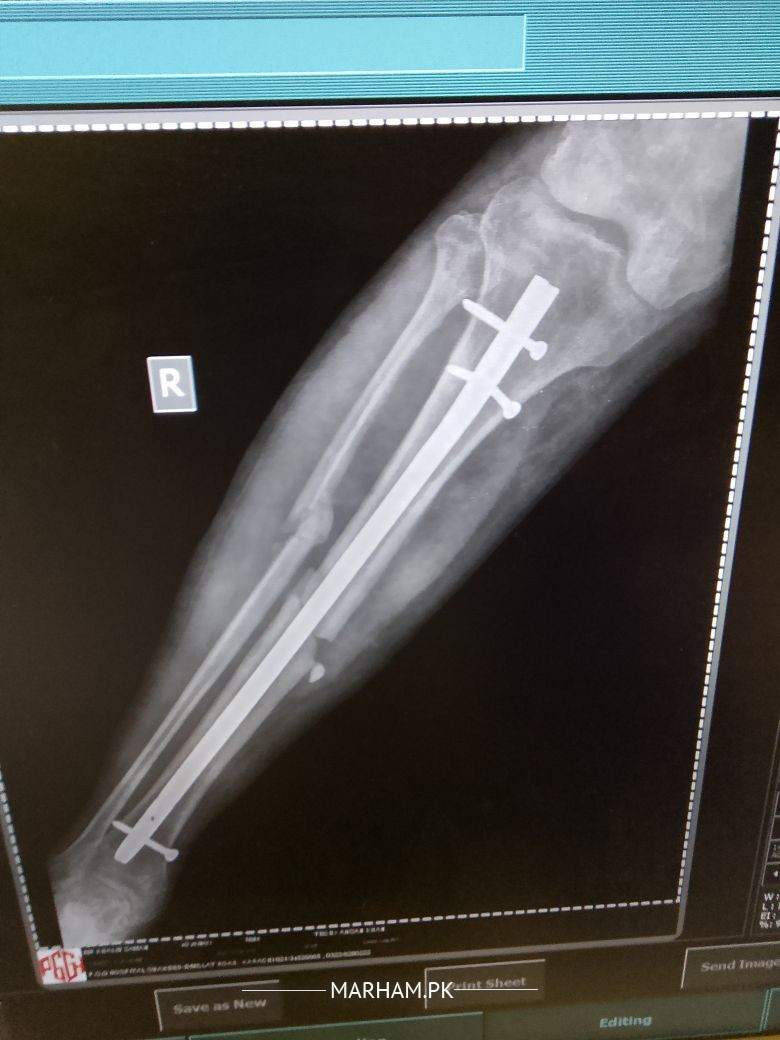

sir mane 5 month pehle opretion keya tha leg ka Lekin mere leg Mai abhi bhi pain ho Raha hai or baghir sahare k nai chal sakta sir plz check my report k Kya reason hai

seems like a case of delayed union. take vit d and calcium supplements and visit orthopaedic nearby. hopefully it will improve.

sir plz reply me k Kya Mai phir opretion karon? q k es Mai haddi ka ik piece hai jes se leg Mai soojan hothi hai or ik keel morh geya hai.plz reply me

Aap ki haddi poori tara se juri nai ay abhi jis ki waja se dard huta ay aapko koi peep waghera aati hai??

sir ye haddi ka Kya karon Jo ik chota sa peace hai